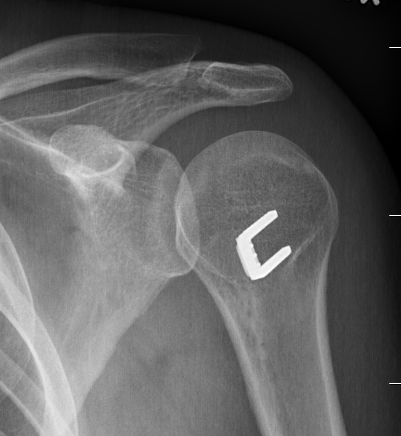

Xray

Traction xray

- patient standing with 5-10 kg in each hand

- inferior subluxation of head